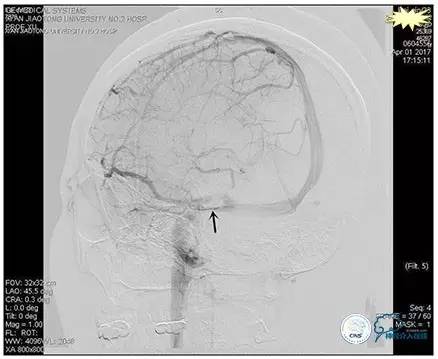

术后造影

术毕远近端压力差为:0

手术方案

1、6mm×20mmAviator球囊(Cordis)分段对狭窄部位进行扩张。

2、植入7mm×40mmPrecise自膨支架。